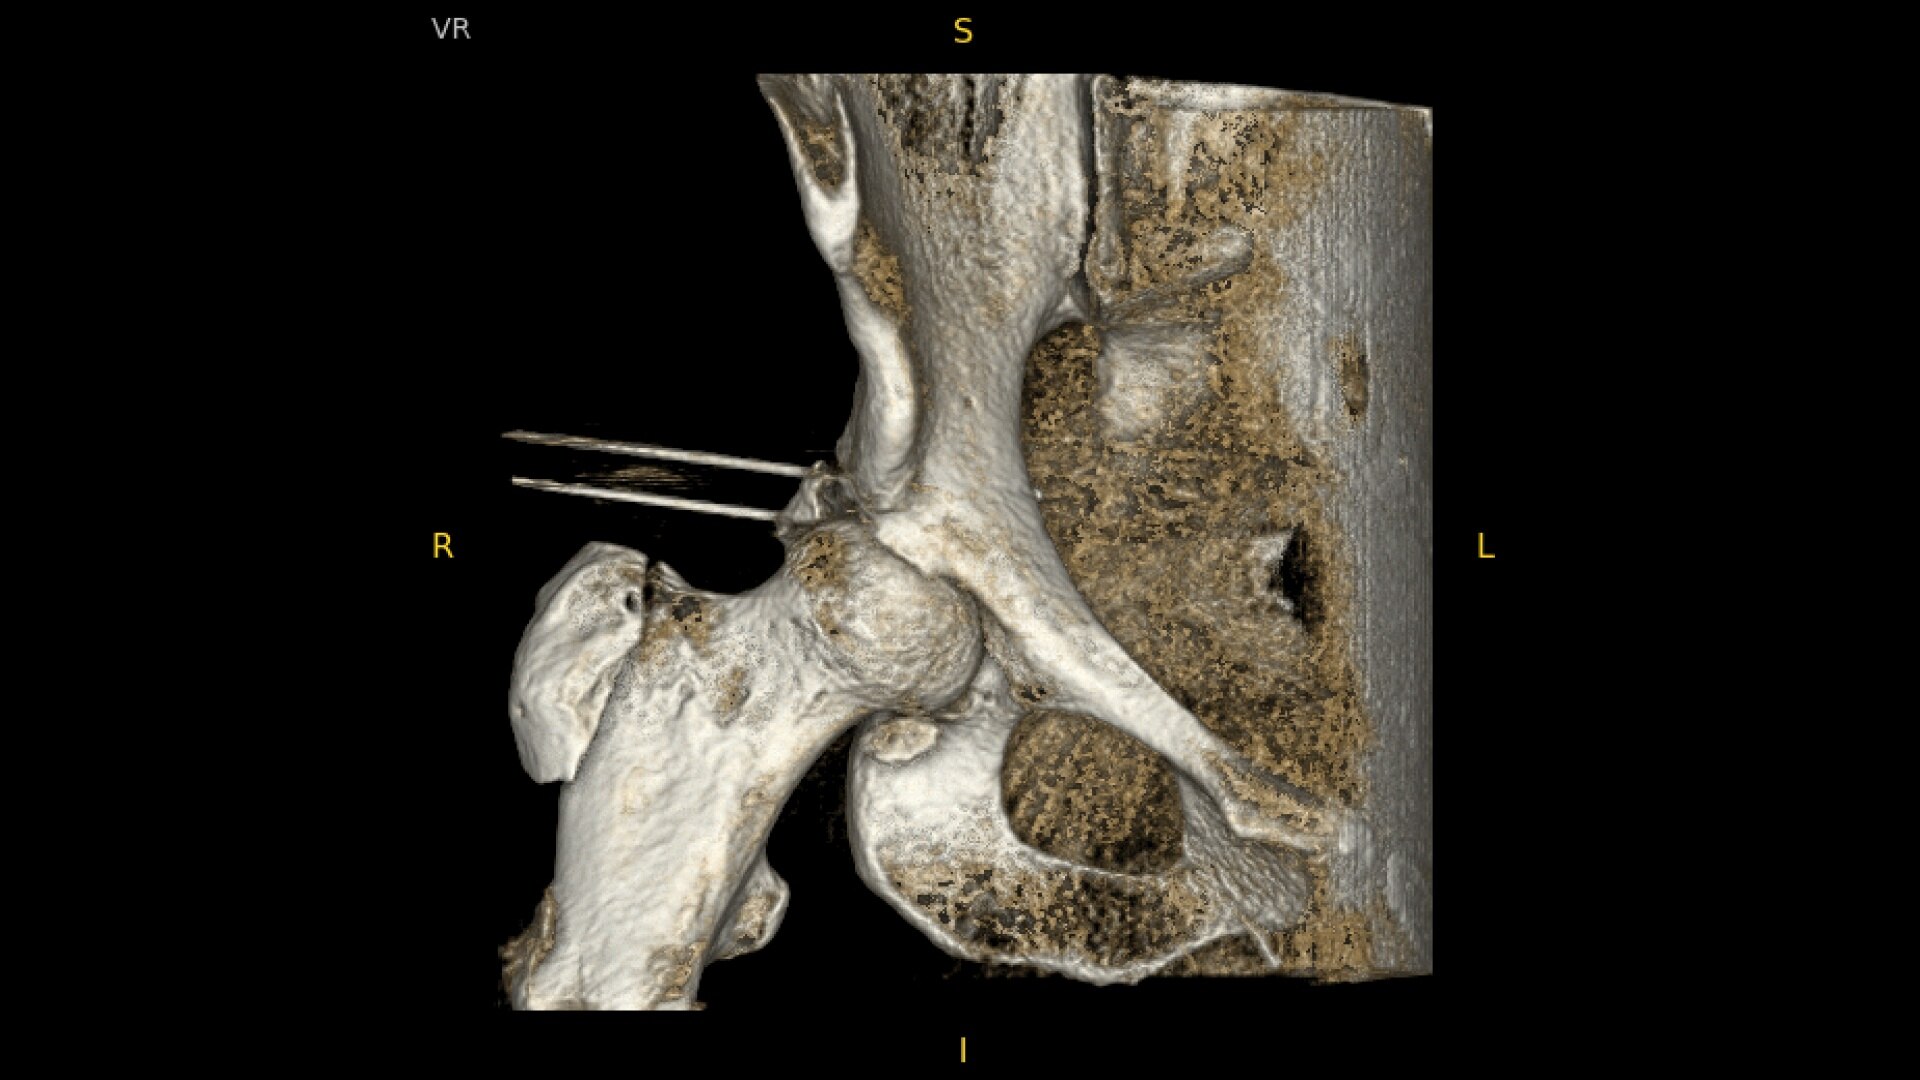

See more levels during a spinal fusion, or more of the pelvis or femur during an orthopedic procedure. With a 19 cm x 19 cm x 19 cm volume, OEC 3D captures a 67% greater volume than other 3D C-arms*.

Enhance intraoperative decision-making with visualization capabilities of Augmented Fluoroscopy in the OEC 3D Volume Viewer. Analyze five perspectives with 3D imaging tools including Multi-Oblique Mode, scrolling 512 slices, zoom, and more.

With an open platform, the OEC 3D can integrate seamlessly with navigation and robotics systems. The OEC Open dedicated port can export high-fidelity 3D data set to navigation or robotics system that accepts DICOM images.